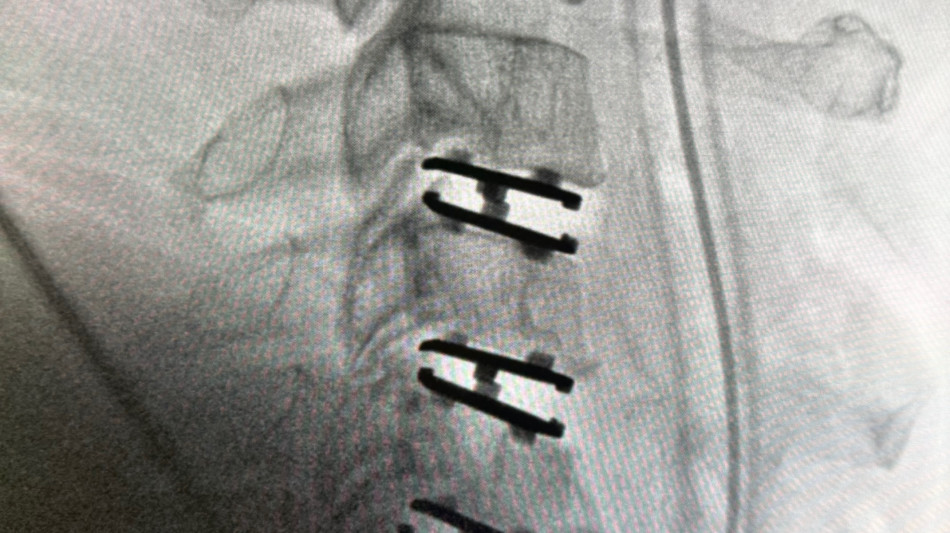

The procedure was performed on Monday at the Advanced Surgery Center of Beverly Hills five weeks after the U.S. Food and Drug Administration (FDA) granted Premarket Approval (PMA) for the Synergy Disc® for single-level cervical disc replacement from C3-C7.

The patient, a 47-year-old man, presented with progressive neck pain, arm pain, and weakness in the setting of spinal cord compression and severe nerve root compression with associated bone spur formation. After failing conservative management, the patient was taken to surgery for a three-level cervical disc replacement to decompress the spinal cord, relieve nerve compression, and remove osteophytic pathology.

The Synergy Disc® is a motion-preserving artificial cervical disc developed by Synergy Spine Solutions and engineered with a lordotic polyethylene core designed to maintain and restore physiologic alignment while allowing controlled motion. The Synergy Disc® is the only artificial cervical disc currently available that combines motion preservation with intentional alignment correction in a single device. The device recently demonstrated superiority to anterior cervical discectomy and fusion (ACDF) in a U.S. Investigational Device Exemption (IDE) clinical trial.